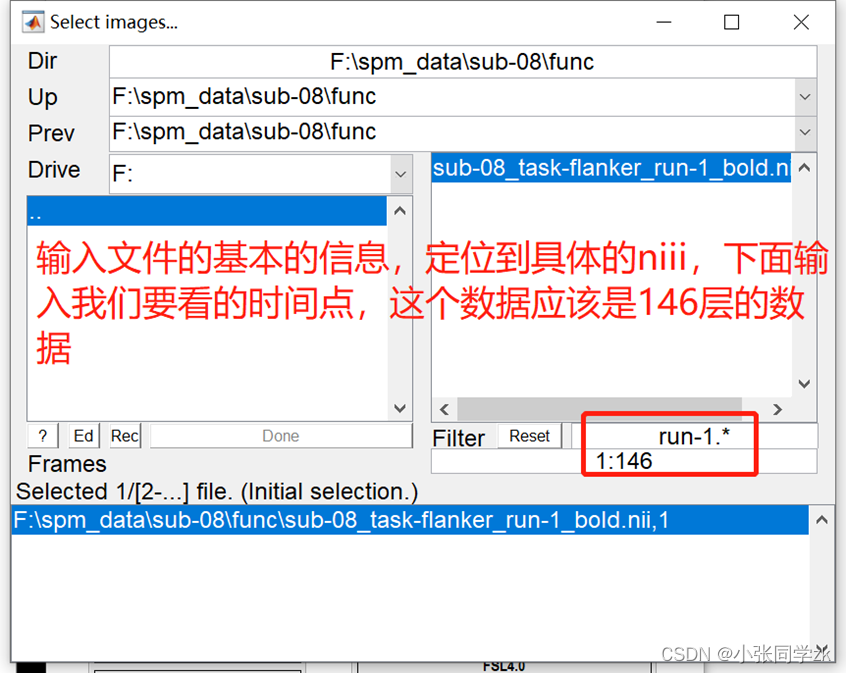

添加数据:双击session按钮,找到需要添加数据的文件夹路径,选择sub-08_task-flanker_run-1_bold.nii,1 “1”是第一个frame或者volume,我们需要在Filters下面输入1:146(如果不知道多少个volumes,就输入1:1000,这样就会把所有的volumes加载进去),然后点击enter,右键select all,点击done,就得到一个run的所有数据。如下图所示。

为了精确找到文件,在 .* 的左边输入run-1。